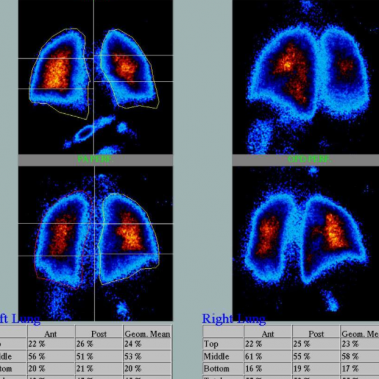

Cenedyt Servicio de Medicina Nuclear se creó hace más de 20 años. Las técnicas de imagen han tenido un desarrollo espectacular en los últimos años y cada vez juegan un papel más relevante en el proceso diagnóstico y terapéutico de los pacientes. El número de exploraciones realizadas es cada vez más elevado.

Estamos especializados en Medicina Nuclear y Densitometría. Nuestro objetivo y ofrecer al paciente la máxima calidad en Diagnóstico y tratamiento, basándonos en nuestra amplia experiencia y últimas tecnologías.